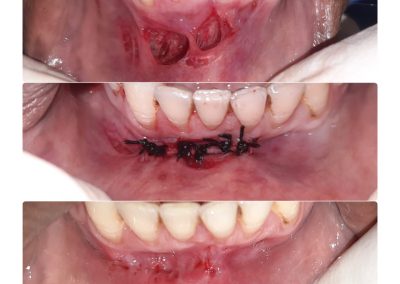

Photo Gallery